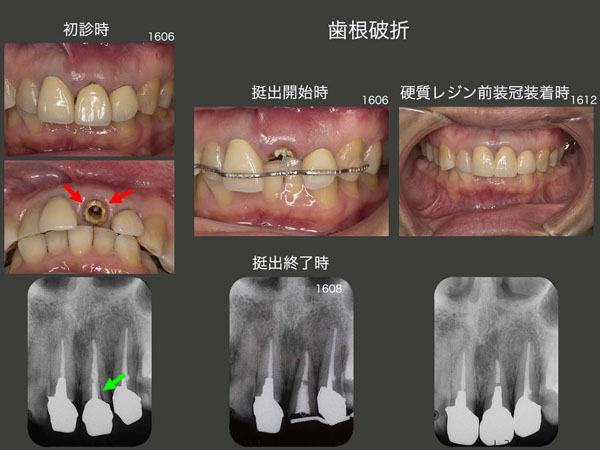

3.歯根破折

2016年6月初診,51歳の女性.左上1が動いて痛いとのことで来院.硬質レジン前装冠を除去してみると,歯根に破折線がみられた(赤矢印).デンタルX線写真からも,透過像が認められた(緑矢印).そこで,16年6月矯正的挺出を開始し,破折部を歯肉縁上に引っ張り出すことにした.8月に,挺出が終了.その後,歯冠長延長術を行い,歯肉縁上歯質を確保した.歯肉が安定するのを待って,12月,硬質レジン前装冠を装着した.